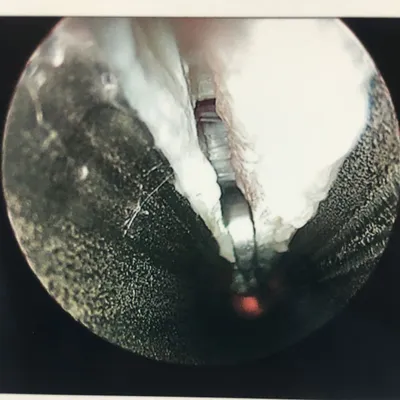

More Intraop Pics of Endoscopic Plantar Fascia Release. The thickened fascia is seen on the left. The Blade is cutting through the fascia in the center pic and confirmation of complete release of that portion of the ligament is noted as we can see the intrinsic muscles after release.